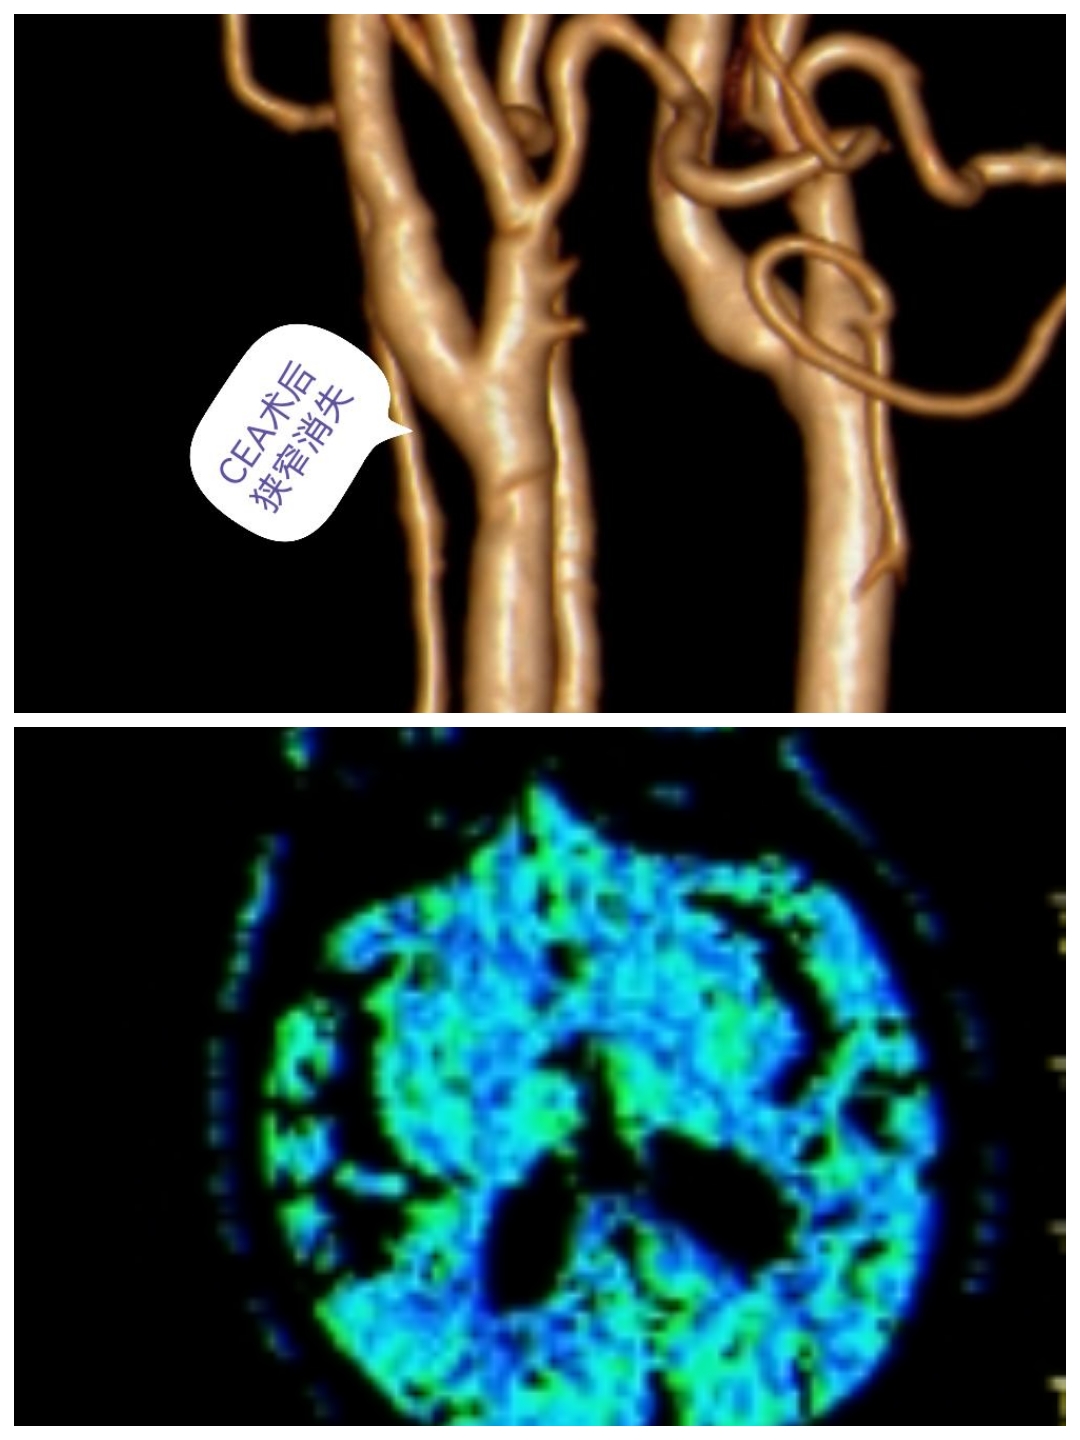

术后随访

CTA提示右侧颈内动脉狭窄消失,患者头晕症状消失